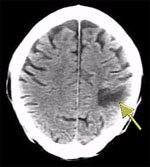

1971年,豪斯菲尔德研制成功的世界上第一台X射线计算机断层扫描机(Computerized Tomography,简称CT)在伦敦一家医院正式安装使用。X射线管在置在患者上方, 绕检查部位旋转, 患者下方的计数器也同时旋转。由于人体器官和组织对X射线的吸收程度不同,病变组织和正常组织对X射线的吸收程度也不同,这些差别反映在计数器上, 经电子计算机处理,便构成了探测对象各个部位的横断图像呈现在荧光屏上,它解决了X射线照相的前后物体图像重叠问题,大大提高了医学诊断的可靠性和准确性,使医学成像技术向前跨了一大步。豪斯菲尔德与神经放射学家阿姆勃劳斯合作,成功地为一名英国妇女诊断出脑部的肿瘤,获得了第一例脑肿瘤的照片。他们在英国放射学会上发表了第一篇论文,1973年英国放射学杂志对此作了正式报道,这篇论文受到了医学界的高度重视,被誉为“放射诊断学史上又一个里程碑”,从此,放射诊断学进人了CT时代。1979年的诺贝尔生理.医学奖破例地授给了豪斯菲尔德和科马克这两位没有专门医学经历的科学家[16]。

最早的CT 机使用单束X 射线,配有1~2 个检测器,扫描时X 射线管每次仅转动1°,完成一次扫描需4~5 分钟。第二代CT 机采用两束X射线构成10°~20°的扇形束, 配有20~30 个检测器, 每次扫描只需30~120秒。第三代CT 机由多个X 射线管组成30°的扇形束, 用250~350个检测器,每次扫描只需2.5秒。第四代CT机用多个X射线管组成50°的扇形束, 用600~2400个检测器排列成环状,扫描时间仅1秒(右图为第四代CT机扫描结构)。CT机正向第五代过渡,只要1/100 秒就可捕捉到人体生理活动的动态信息。 最早的CT 机使用单束X 射线,配有1~2 个检测器,扫描时X 射线管每次仅转动1°,完成一次扫描需4~5 分钟。第二代CT 机采用两束X射线构成10°~20°的扇形束, 配有20~30 个检测器, 每次扫描只需30~120秒。第三代CT 机由多个X 射线管组成30°的扇形束, 用250~350个检测器,每次扫描只需2.5秒。第四代CT机用多个X射线管组成50°的扇形束, 用600~2400个检测器排列成环状,扫描时间仅1秒(右图为第四代CT机扫描结构)。CT机正向第五代过渡,只要1/100 秒就可捕捉到人体生理活动的动态信息。